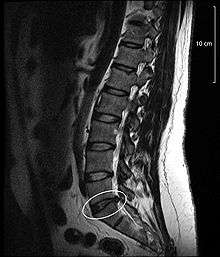

A disc protrusion is a disease condition which can occur in some vertebrates, including humans, in which the outermost layers of the anulus fibrosus of the intervertebral discs of the spine are intact, but bulge when one or more of the discs are under pressure.

Many disk abnormalities seen on MRI that are loosely referred to "herniation" are actually just incidental findings. These may be unrelated to any symptoms and are just bulges of the annulus fibrosus. Jensen and colleagues, in an MRI study of the lumbar spine in 98 asymptomatic adults, found that in more than half, there was a symmetrical extension of a disc (or discs) beyond the margins of the interspace (bulging). In 27 percent, there was a focal or asymmetrical extension of the disc beyond the margin of the interspace (protrusion), and in only 1 percent was there more extreme extension of the disc (extrusion or sequestration). These findings emphasize the importance of using precise terms in describing the imaging abnormalities and evaluating them strictly in the context of the patient's symptoms.[1]

A disc protrusion may progress to a spinal disc herniation, a condition in which there is a tear in the anulus fibrosus.